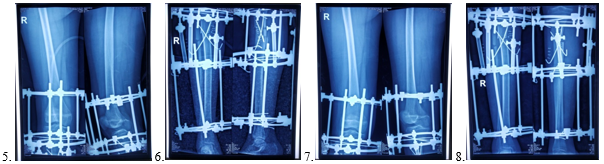

5 & 6 Post-operative x-ray 7 & 8 Follow up x-ray.

Upper tibial corticotomy was done at obvious apex (at the point of maximum angulation) by giving least incision on medial surface of right upper leg. Fibulectomy (Rt. fibula) also done. Bony fragments were fixed by Ilizarov frame with two cross k-wire for stability and maintain alignment. Four Ilizarov circular rings were used. One ring placed in distal femur and another in proximal tibia above corticotomy line to maintain joint space. Other two rings placed in tibia below the corticotomy. All rings were fixed by k-wire with bone and 2 olive wires used in middle 2 rings. Rings were connected by threaded rods to each other, in addition middle 2 rings (Rings are set above and below the corticotomy) are connected by two telescopic rods on medial and lateral side of leg parallel to medial and lateral surface of tibia. The Ilizarov frame provides stability and maintains alignment.

Surgery duration 1 hour and 30 minutes (90 minutes), total blood loss about 120 ml. Tourniquet was not used during surgery. Bony fragments were in anatomical alignment and adequate fixation stability maintained. Partial weight bearing walking started on 3rd POD with walker. Hospital stays 5 days. Stitch off done on 12th POD. After 3 weeks when callus appeared k-wires were removed and bone lengthening with angulation correction was started at a rate of 0.25 mm x 4 times (6 hourly) in a day by loosening of lateral telescopic rod for 10 days. Total one (1) cm bone lengthening was done of lateral tibial surface. Angulation and length were corrected to our desire and restoration of normal mechanical axis.

Patient and relatives were trained up to clean and proper maintained Ilizarov frame to avoid pin track infection. Also encourage the patient to regular walking with hip and ankle joint movement by exercise. Patient came in F/U weekly for 1 month, 2 weekly for next month and finally once in a month until full recovery. After 3 months, when callus became consolidate, Ilizarov frame removed and apply long leg full plaster for another 6 weeks. After plaster removal knee joint mobilization was done and within 5 months of corticotomy, full recovery was regain with full ROM of all joint of right lower limb. There was 0.5 cm shortening of right lower limb which was corrected by high heel shoe.